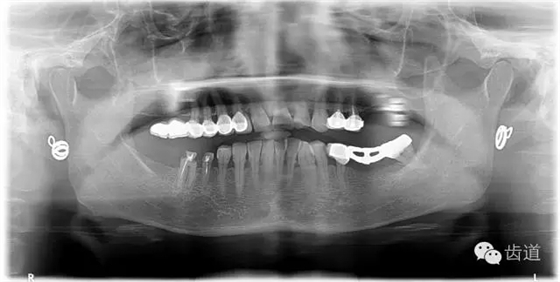

1、術(shù)前全景片

2、45,46術(shù)前片顯示根管上段充填物,根管影像不清晰,少許根尖暗影

1、治療前